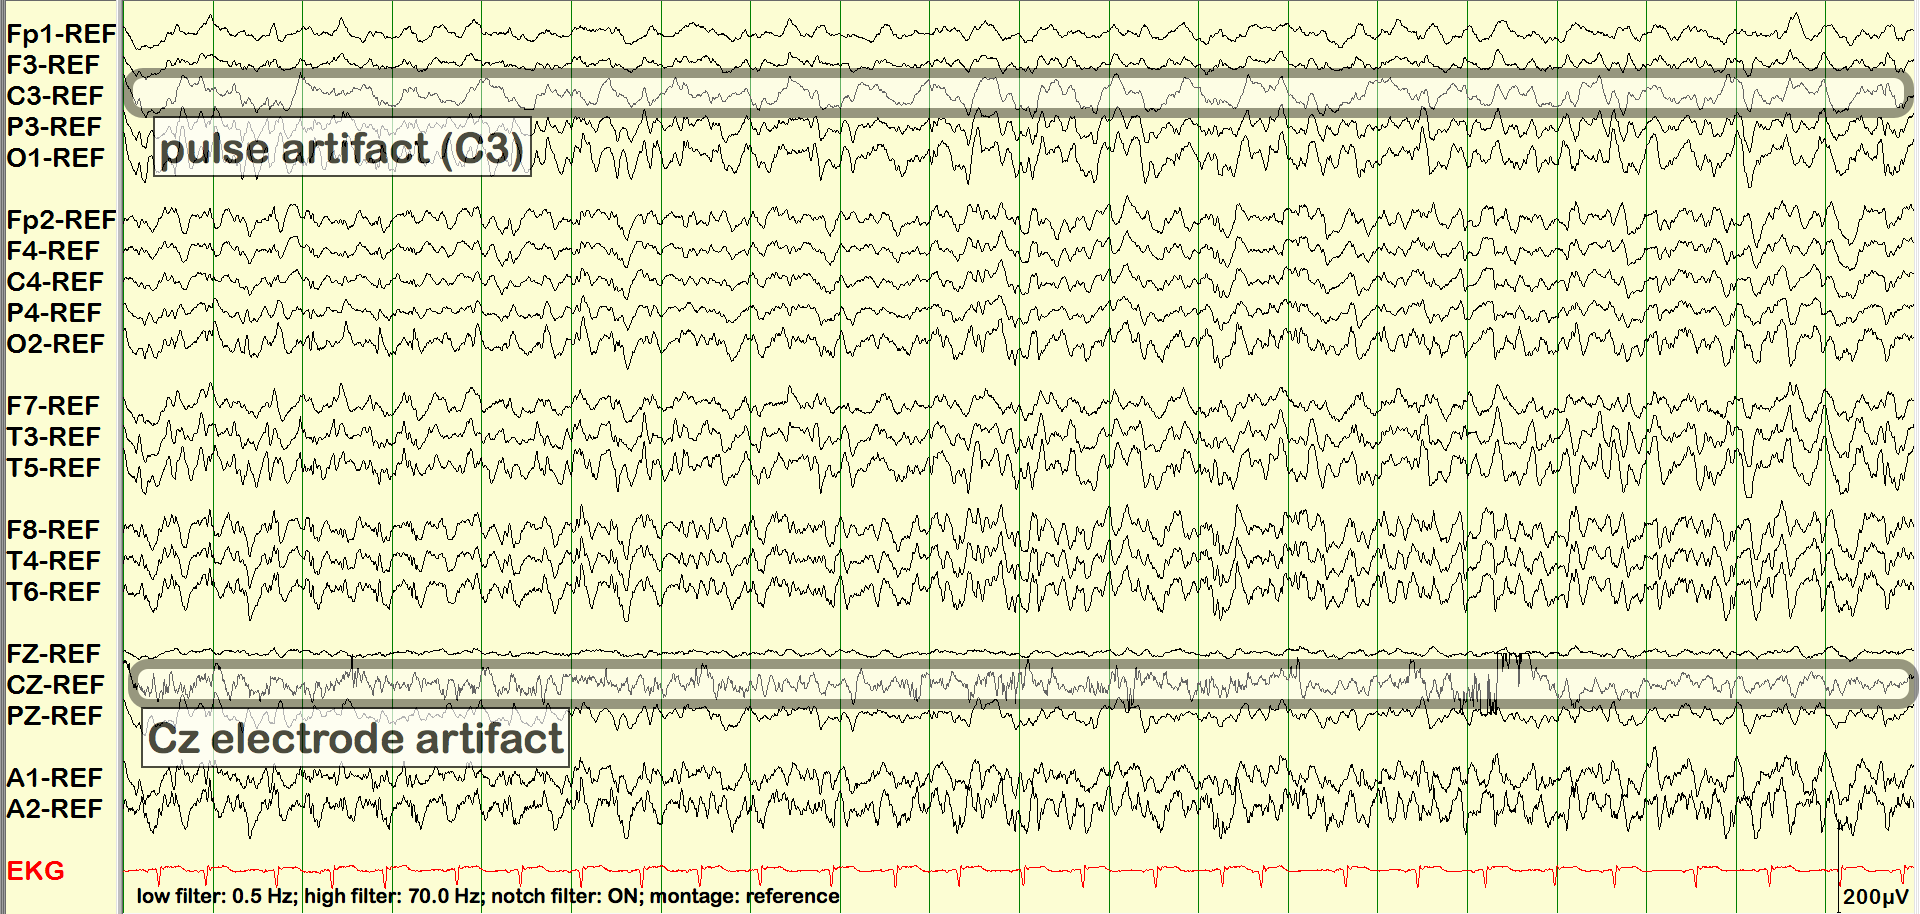

Pulse Artifact

In the following example, the pulse artifact in C3 is seen to stay synchronized with the EKG over the entire 3 minute and 15 second clip.